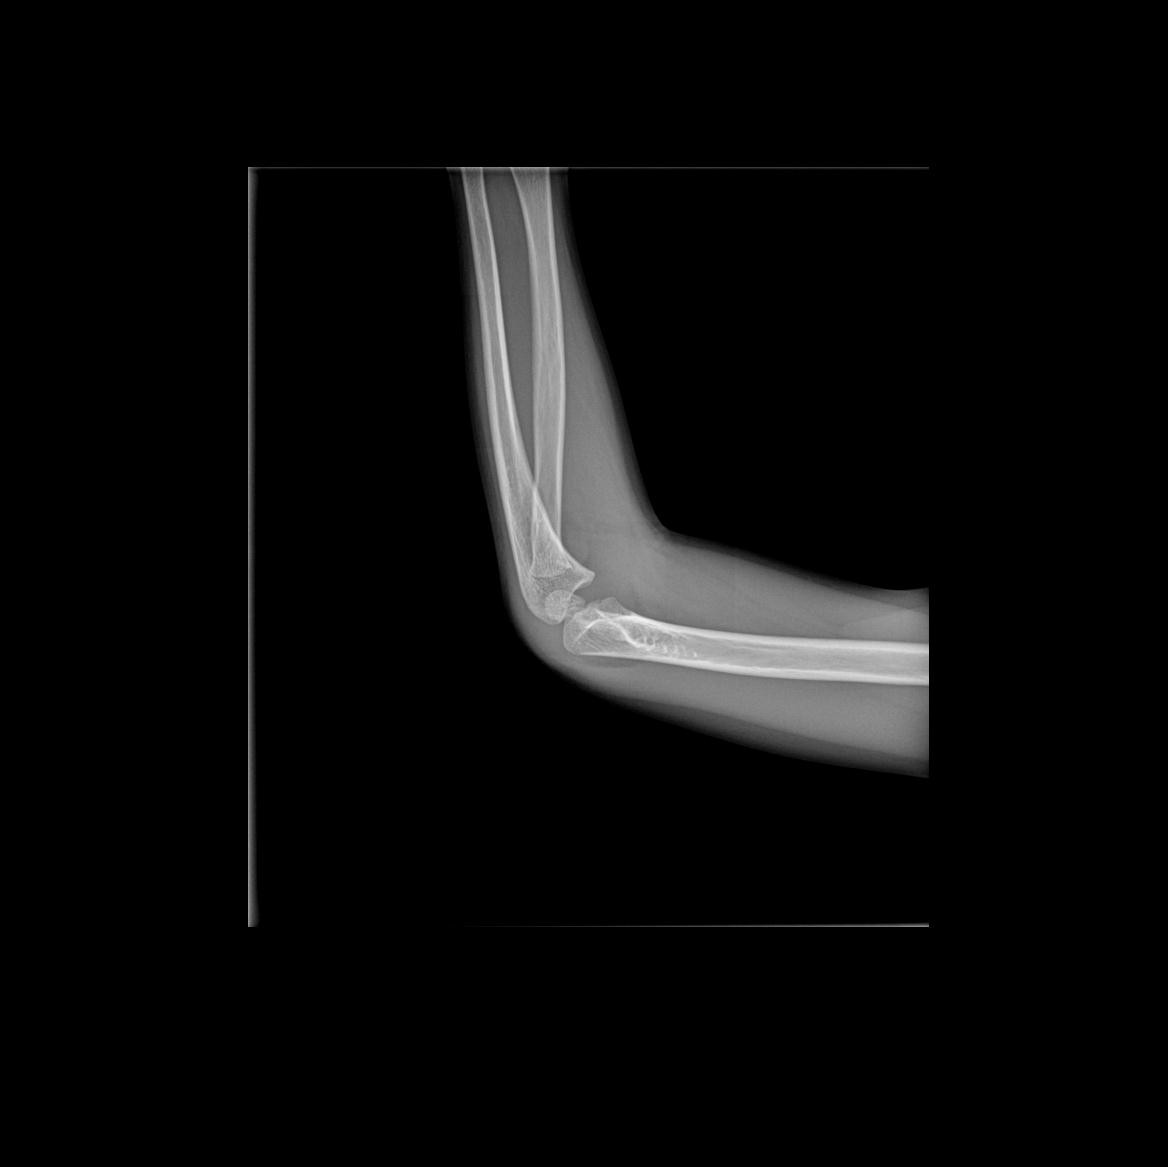

Перелом левой плечевой кости у ребенка

Здравствуйте, помогите пожалуйста! 09.09.2021 ребенок упал с турника с небольшой высоты но рядом стоял пень и при падении ребенок ударился об него рукой. Заключение врача и снимки выложу ниже! Положили гипс от плеча до середины пальцев. У меня такие вопросы.

1. Правильно 2. Гипс правильный. Альтернативы - полимерные материалы 3. Косыночный бандаж для поддержки будет полезен